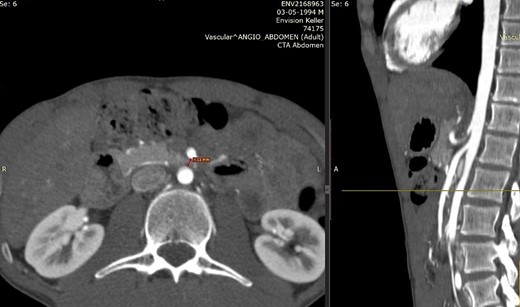

The diagnosis is usually delayed due to lack of knowledge of the disease. Useful diagnostic modalities are computed tomography (CT) as a standard tool, and ultrasonography [3, 6]. CT with mesenteric angiography helps determine the measurement of the aortomesenteric angle, being the main anatomical characteristic of this syndrome the narrowing of the angle between the SMA and the aorta to ≤25°, being the normal 38 to 65° [6, 7]. This narrowing leads to compression of the third portion of the duodenum as it crosses between the aorta and the SMA, and may even result in compression of the left renal vein. The aortomesenteric distance is reduced from the normal 10–28 mm to 2–8 mm, and the severity of the symptoms is related to the aorta – SMA distance [8]. Therefore, an aortomesenteric angle less than 22° and a distance less than 8 mm on contrast-enhanced CT angiography are consistent with SMAS [7].

We present the case of a 21-year-old male patient, with a history of laparoscopic cholecystectomy and 3 cryoablations for Barret’s esophagus with grade III dysplasia, who presented with persistent postprandial vomiting that had caused weight loss of 11 kg in the last 2 years without apparent cause, associated with gastroesophageal reflux that has worsened over time, occasional stabbing abdominal pain in the epigastrium, painful constipation, bloody stools and steatorrhea, managed clinically and symptomatologically without improvement in the condition. On evaluation, the patient was thin, with a BMI of 17.31 kg/m2, and in paraclinics, in endoscopy (Figs 1 and 2), Barret’s esophagus and hiatal hernia; In tomography (Figs 3 and 4), an aortomesenteric angle of 17.5°, with aortomesenteric distance of 4 mm.

Computed tomography. Aortomesenteric distance of 4 mm. Wilkie’s syndrome.